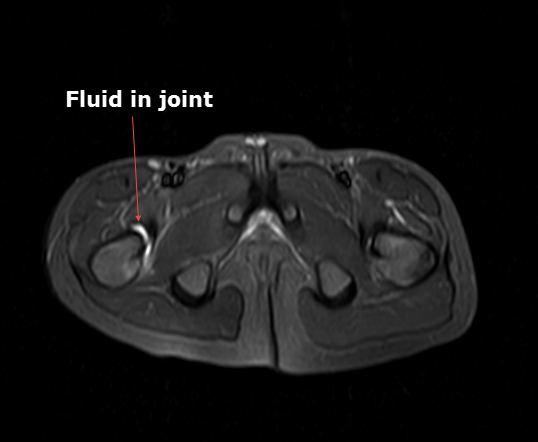

4. MRI

T2영상에서 신호강도가 높은 활액의 증가소견이 관찰됩니다. 대퇴골이나 골반골의 신호강도 변화는 관찰되지 않아야 합니다.